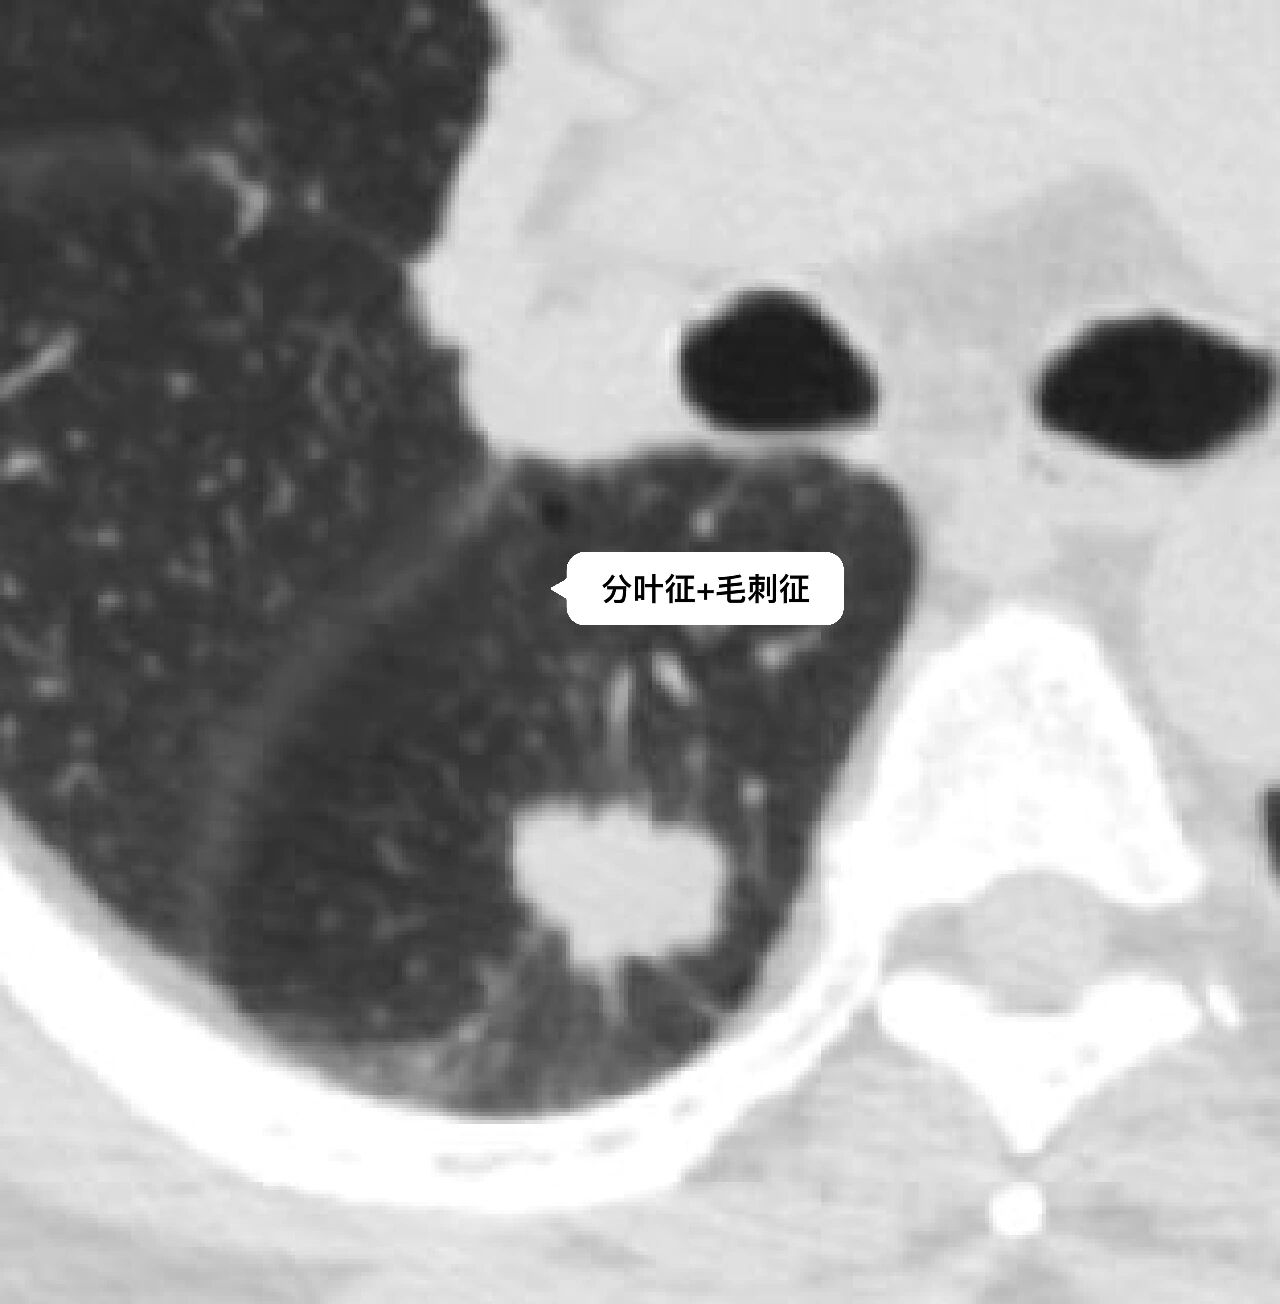

分叶征 毛刺征

周围型肺癌征象之分叶征,毛刺征,棘状突起

棘状突起:肿瘤细胞局部浸润,是介于分叶和毛刺之间粗钝的杵状结构2.